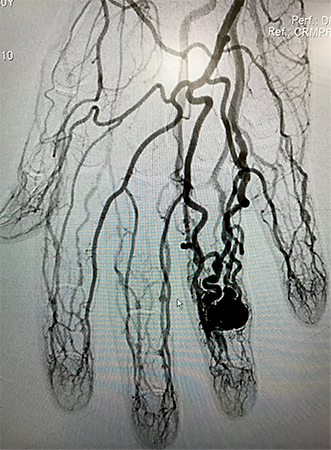

Quimioembolização Hepática

O hepatocarcinoma é o câncer primário do fígado mais comum na população. Geralmente associado à cirrose hepática, e hepatite C ou B crônica. Menos da metade dos pacientes tem condições de ressecar o tumor através de uma hepatectomia no momento do diagnóstico. O tratamento do tumor através da injeção de quimioterápico por cateterismo, é uma forma de tratamento que pode auxiliar em muito no controle da doença. Através do cateterismo de uma artéria femoral (virilha) ou braquial (cotovelo), o cirurgião vascular navega pela circulação arterial chegando o mais próximo possível do tumor. Então, injeta o quimioterápico, geralmente combinado com pequenas partículas, com a intenção de impregnar o tumor com uma alta concentração de droga, além de reduzir a sua nutrição sanguínea, obstruindo as artérias que levam fluxo até ele.

Usualmente o paciente recebe alta no dia seguinte ao procedimento, com efeitos colaterais muito leves, por vezes até ausentes. Quem indica este procedimento é o médico responsável pelo tratamento do câncer, seja um oncologista ou um hepatologista.